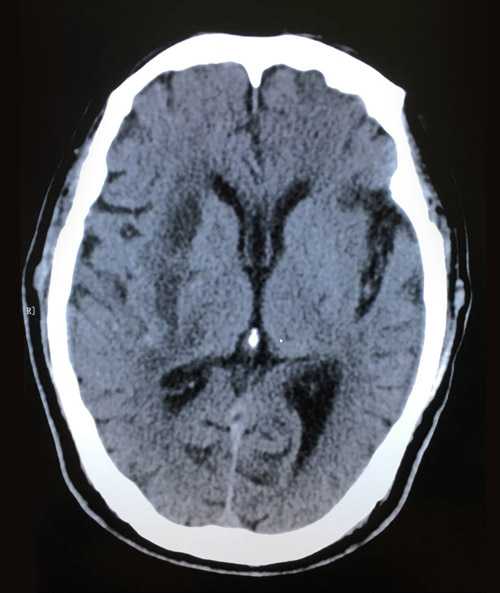

术后影像:脑出血引流术后,几乎看不到血肿残余

现在秦大爷已转回普通病房,饮食,睡眠都恢复如常,肢体活动也在慢慢恢复,再过不久就可出院了。